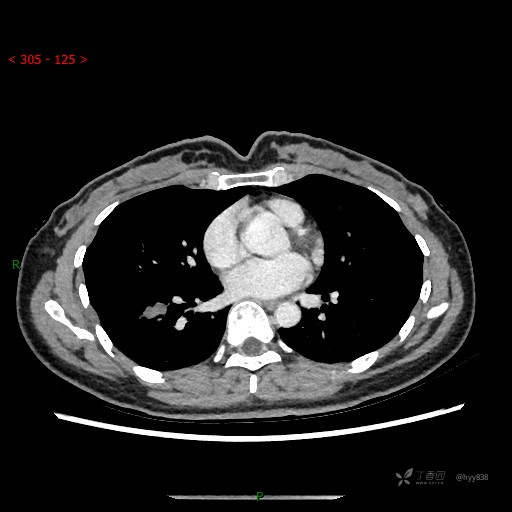

胸部CT平扫

增强动脉期

静脉期

CT值